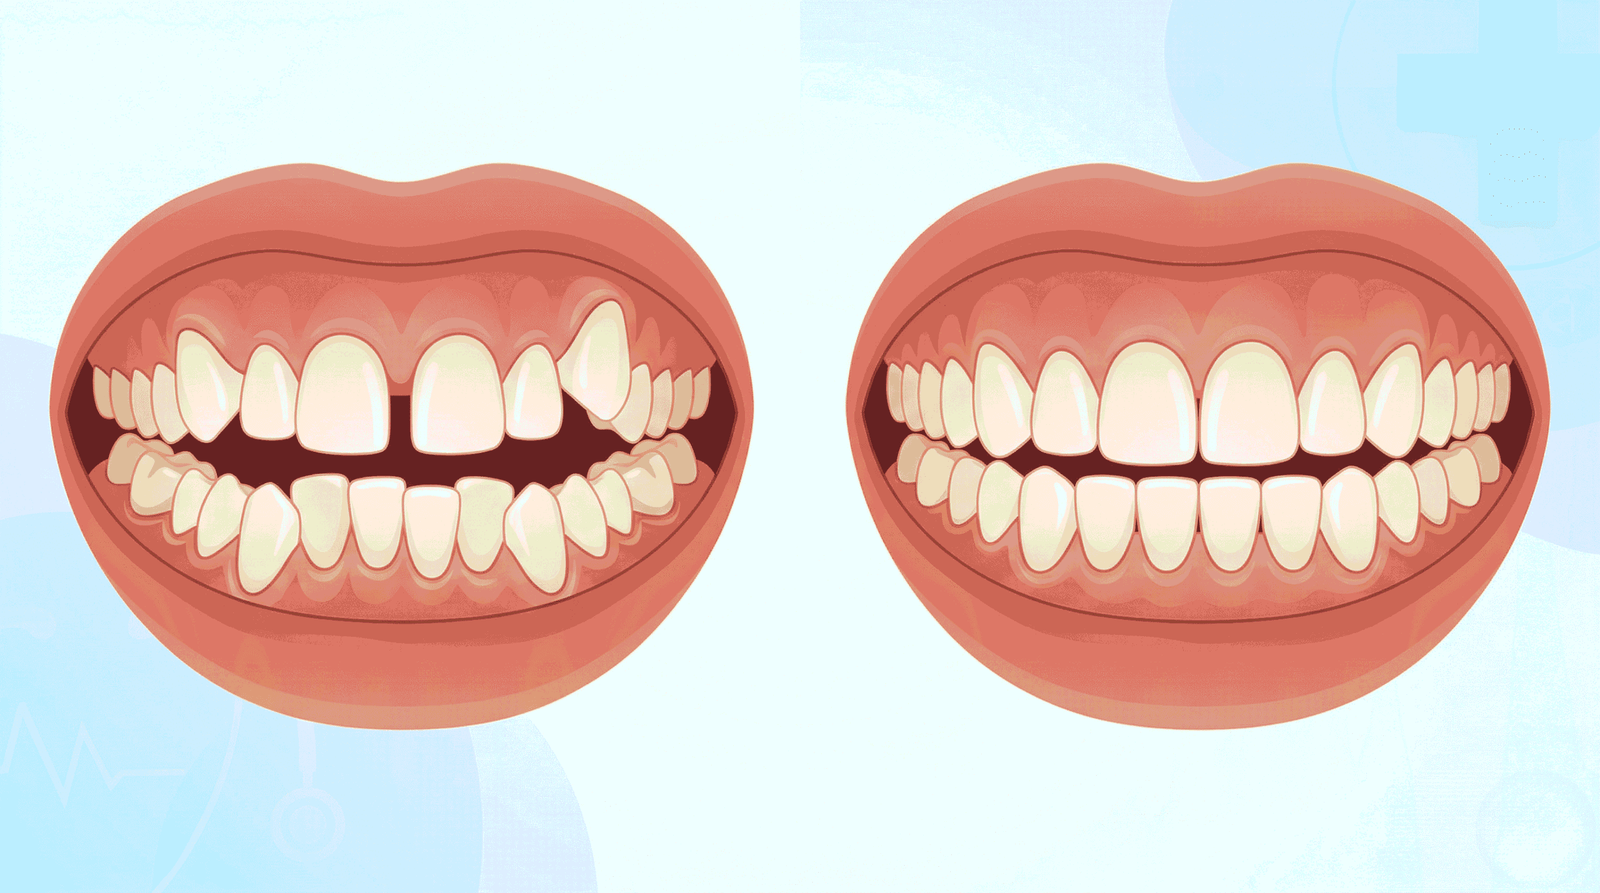

1. تزاحم الأسنان (Crowding)

حين ترون أسنانكم متراصّة ومتداخلة، أو يظهر سن فوق آخر، فهذا ما يُعرف بـ”التزاحم” — وهو الحالة الأكثر شيوعاً في عيادتنا. يُفضي التزاحم إلى مناطق يصعب تنظيفها بالفرشاة والخيط الطبي، مما يرفع معدلات التسوس والتهاب اللثة بصورة ملحوظة.

والتزاحم الشديد ليس مشكلة شكلية فحسب؛ إذ قد يؤثر على جذور الأسنان المجاورة إذا أُهمل علاجه.

2. الفراغات والمسافات الزائدة بين الأسنان (Spacing)

على العكس تماماً — إذا كانت هناك مسافات واسعة بين الأسنان سواء الأمامية أو الجانبية، فقد يعود ذلك إلى أسنان أصغر من المعدل الطبيعي، أو أسنان مفقودة خلقياً أو إثر خلع، أو عادة ضغط اللسان على الأسنان. هذه الفراغات تُسبب خللاً وظيفياً في المضغ وتؤثر أحياناً على الكلام.